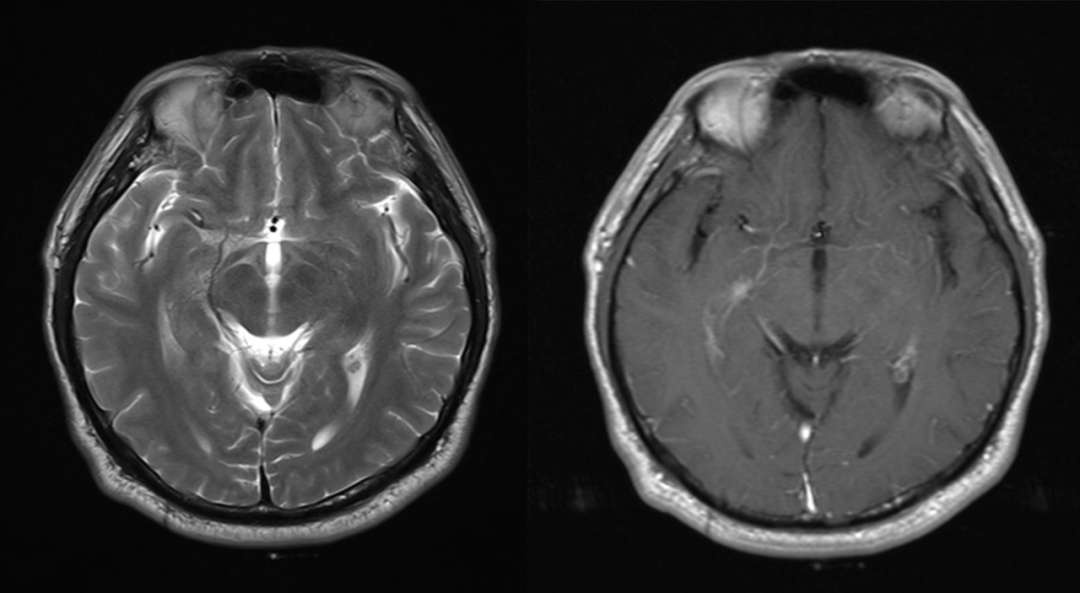

女,55 岁,肺腺癌患者。检查颅脑核磁增强是否存在转移瘤。

首次检查 2021-1-5 日发现左侧颞叶强化结节,轴矢冠状位都能看到,但是平扫看不到,周围亦未见水肿信号,此时没经验的诊断医生估计会考虑为转移瘤,一直困扰着患者和临床医生。但是在其余 7 次检查中 2021-3-2 至 2022-6-22 一年半多的时间,左侧颞叶强化结节仍然存在,并且基本没啥变化,如果是转移瘤会这么长时间无任何干预都处于一个静止状态吗?,此时是不是需要考虑其他的诊断?,究竟是什么呢,有经验的医生肯定会想到:是毛细血管扩张症。

仔细观察本例左侧颞叶强化结节,中心为明显强化,周围为稍淡淡样的强化,此为毛细血管扩张症的特点。